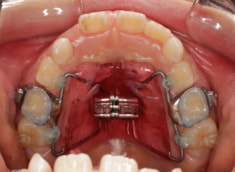

治療開始から11ヶ月